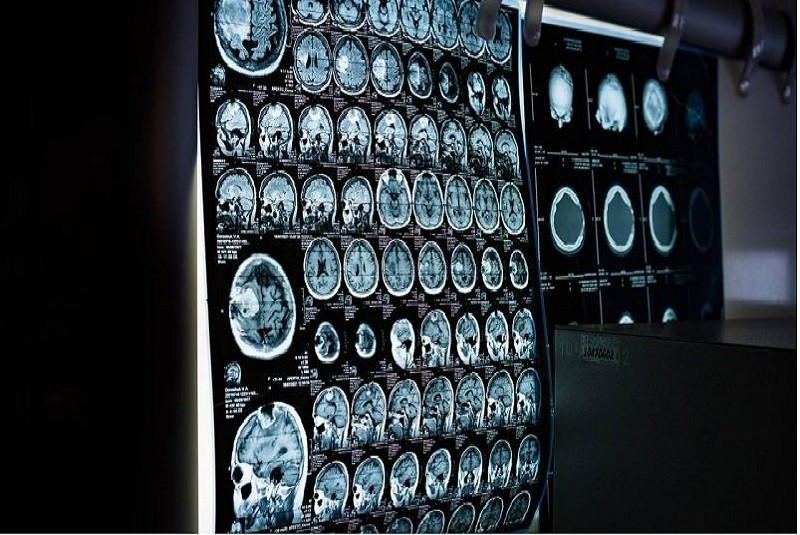

Los investigadores utilizaron resonancias magnéticas funcionales (fMRI), de mil 100 voluntarios del Biobanco del Reino Unido, y se centraron en la “red de modo predeterminado” (DMN) del cerebro, conocida por ser especialmente vulnerable a la enfermedad de Alzheimer.

Los escaneos, que miden la actividad cerebral en estado de reposo, revelaron cambios en la conectividad entre regiones cerebrales en aquellos que posteriormente desarrollaron demencia.